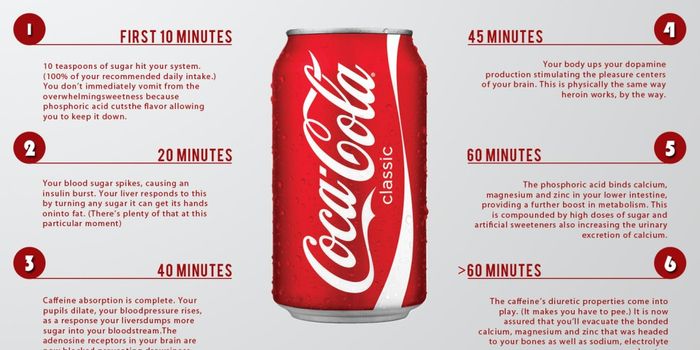

JUL 30, 2015Health & MedicineCoca-Cola is a very popular soft drink; if a restaurant doesn't have Coke dispensers, it probably has its competing bran ...